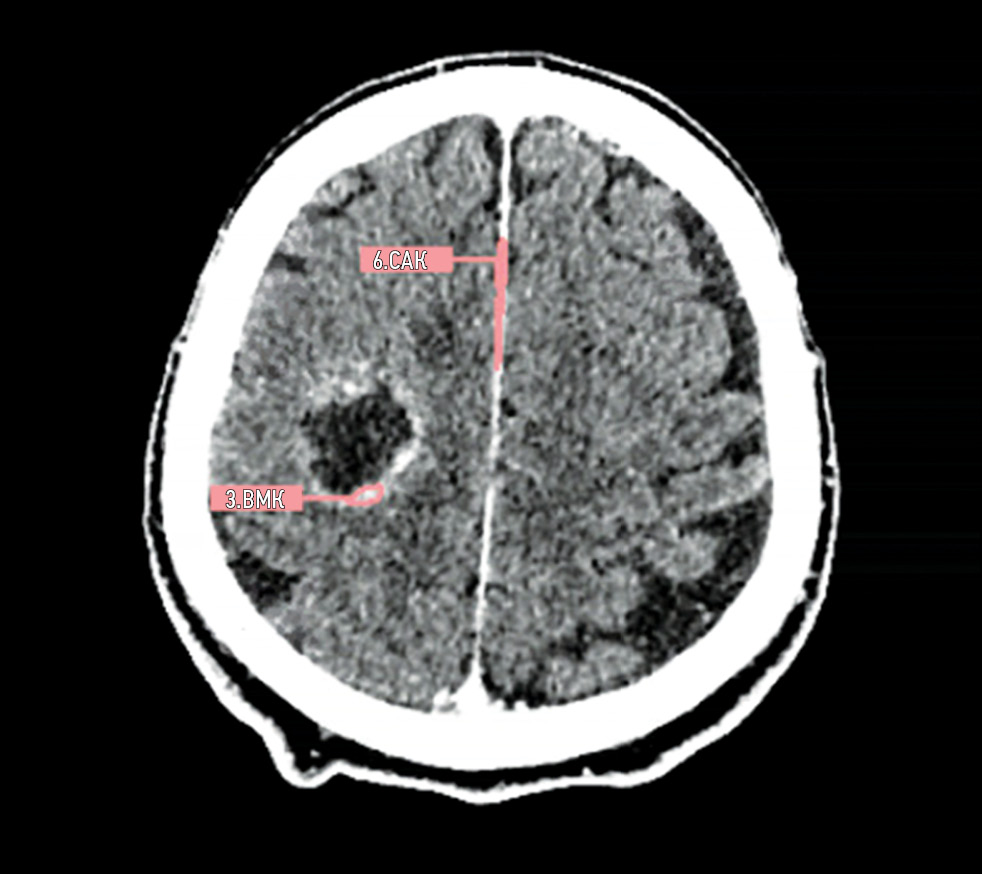

Figures 3, 4, 5, and 6 show examples of technological errors in AI-based software.

Fig. 5. Defect: an incorrect series was evaluated (contrast-enhanced computed tomography instead of native on). Modality: computed tomography.

Fig. 6. Defect: off-target markings, contrast-enhanced computed tomography instead of native computed tomography. Modality: computed tomography.